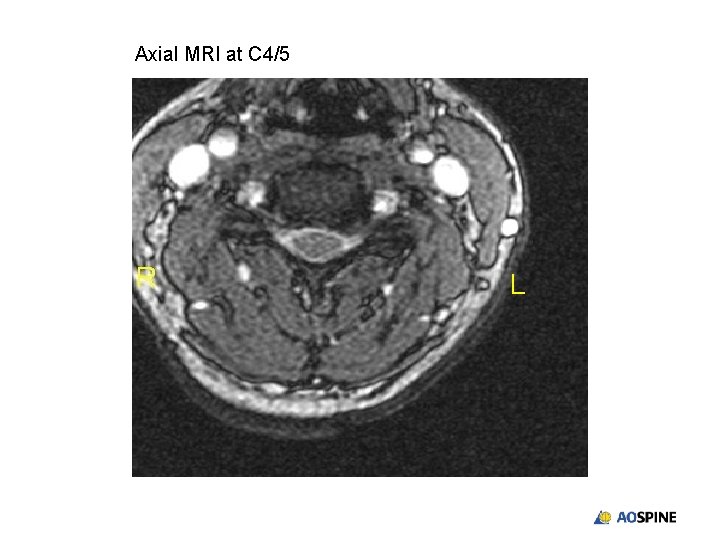

Axial MRI at C 4/5 L

Summary • Adjacent segment disease after anterior cervical discectomy and fusion presents with both mechanical and neurological symptoms • C 4/5 uncovertebral osteophytes responsible for left C 5 radiculopathy • CT myelogram most accurately reflects degree of compression on neural root • Central stenosis may be minimal • Surgical options include anterior or posterior decompression, depending on degree of mechanical symptoms • Restoration of disc height indirectly decompresses foramen and exiting nerve root